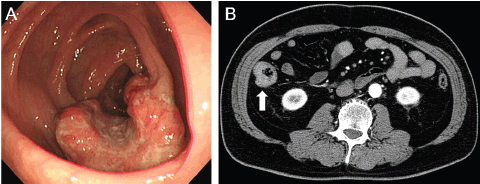

The patient had no symptoms. Physical examination revealed no abnormalities, and there was no evidence of an abdominal mass or peripheral lymphadenopathy. Laboratory tests revealed hyperglycaemia and hyperlipidaemia. Colonoscopy demonstrated an ulcerated tumour in the ascending colon (Figure 1A). Moderately differentiated adenocarcinoma was detected in the biopsy specimen taken from the tumour. Computed tomography (CT) scanning of the neck, chest, abdomen, and pelvis revealed a mucosal thickness in the ascending colon, but there were no lymph node swellings or metastatic lesions (Figure 1B). Consequently, the diagnosis of colon cancer, localised in the colon, was made.

Figure 1. Images of the ascending colon with a cancerous lesion. (A) Colonoscopy examinations show an ulcerated tumour in the ascending colon. (B) CT scanning with contrast media reveals a mucosal thickness in the ascending colon without lymph node involvement or metastatic tumours.